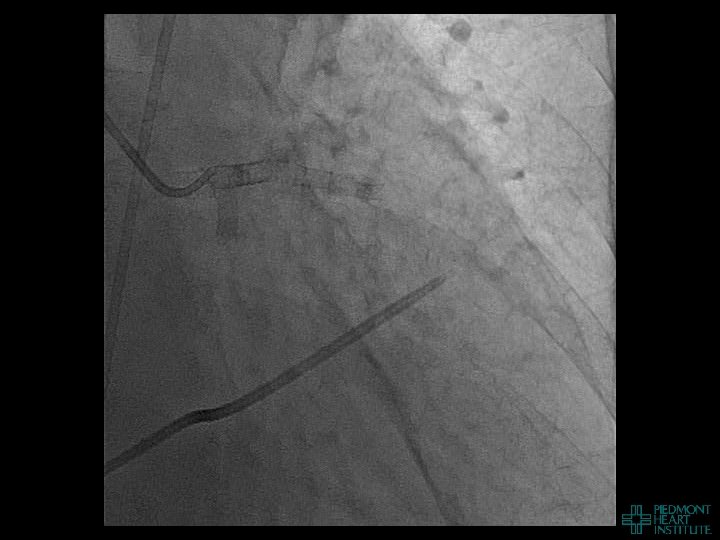

Coronary Perforation Methods of Patient Management • Dual Catheter (‘Ping Pong’) Technique • Prolonged

Coronary Perforation Methods of Patient Management • Dual Catheter (‘Ping Pong’) Technique • Prolonged balloon inflation and covered stents • Reversal of anticoagulation — Know contradictions to protamine sulfate for UFH; Avoid bivalirudin, LMWH — Reserve GP 2 b 3 a inhibition until successful crossing and wire change-out Embolization • — Coil, gelfoam, methacrylate, autologous blood/fat • Microcatheter Occlusion • Confirmation of successful management — Contralateral injection — Right heart catheterization — Echocardiogram — Contrast echocardiography